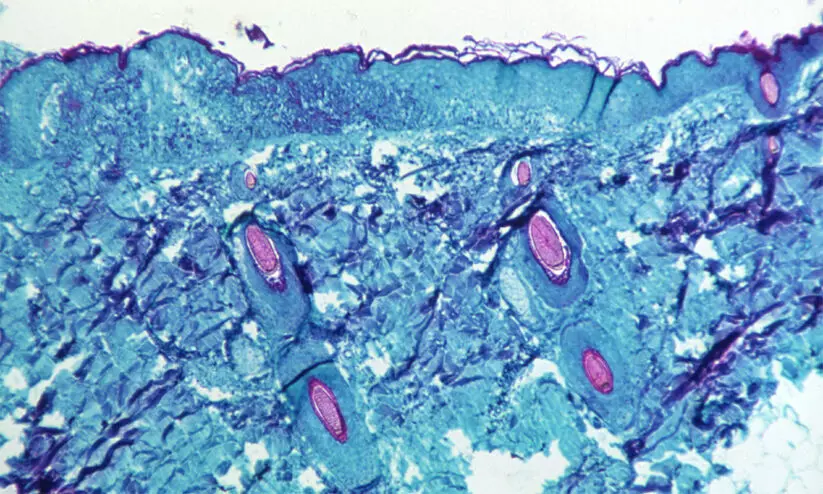

മങ്കി പോക്സ്: പ്രതിരോധ പ്രവർത്തനങ്ങളുമായി ആരോഗ്യ വകുപ്പ്

text_fieldsതിരുവനന്തപുരം: മങ്കി പോക്സിനെ പ്രതിരോധിക്കാൻ ശക്തമായ നീക്കങ്ങളുമായി ആരോഗ്യ വകുപ്പ്. സംസ്ഥാനത്ത് ഒരാൾക്ക് മങ്കി പോക്സ് സ്ഥിരീകരിക്കുകയും മറ്റൊരാൾ രോഗം സംശയിക്കപ്പെട്ട് ചികിത്സയിലിരിക്കുകയും ചെയ്യുന്ന സാഹചര്യത്തിലാണ് ആരോഗ്യ വകുപ്പിന്റെ നടപടി.